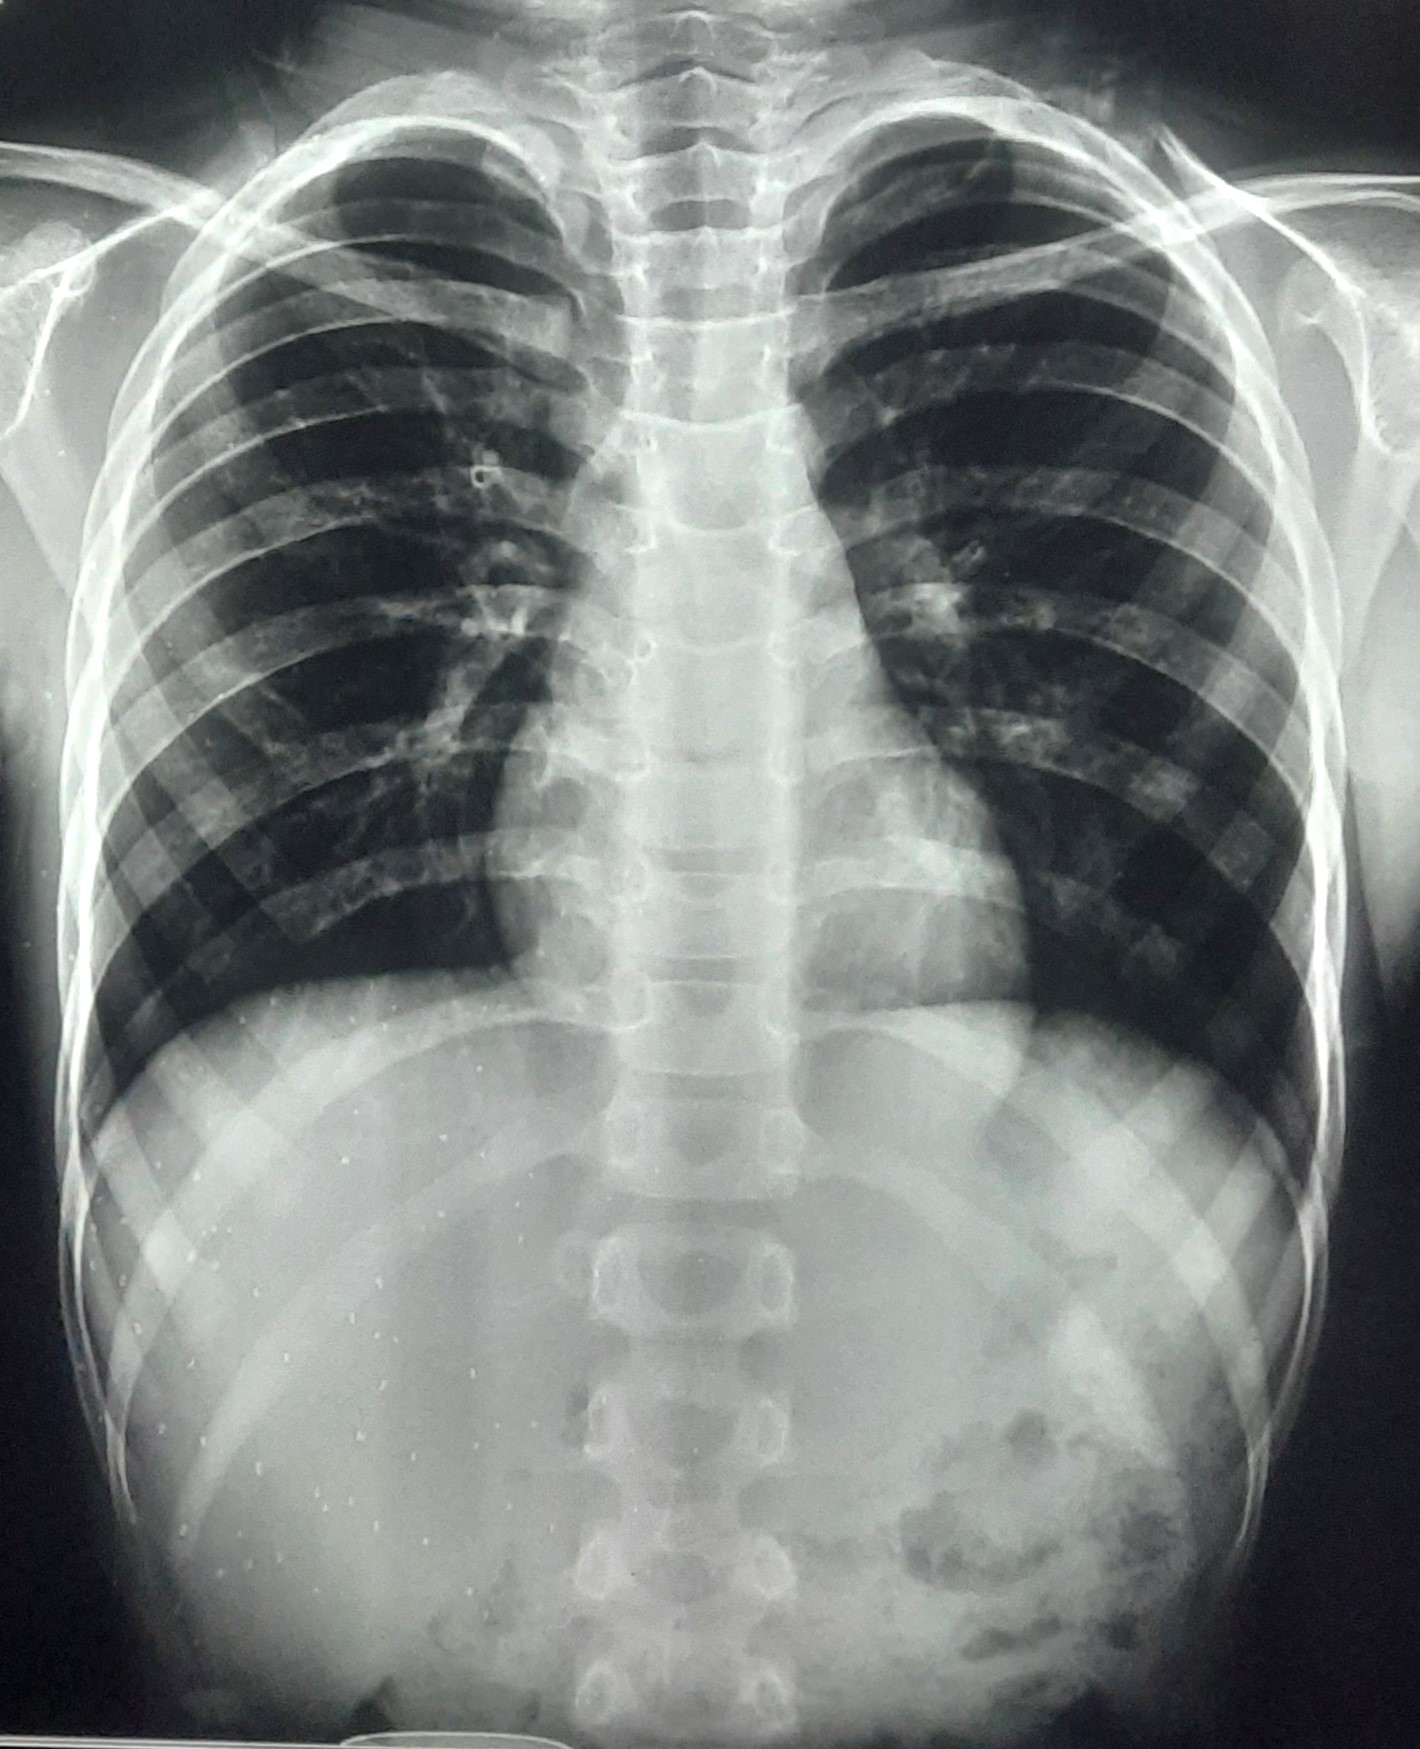

| 330 | IGGMC, Nagpur, Nagpur | P2 | 29-4142 | Pravin Chauhan | Consent taken on Paper | 72 Yrs. |

Provisional Diag : Post TB Sequelae

Final Diag : Post TB sequalae COAD With Right Upper Zone Fibrosis With Bilateral Bronchiectasis In Exacerbation |

Post TB Sequelae | Abnormality visible on x-ray |